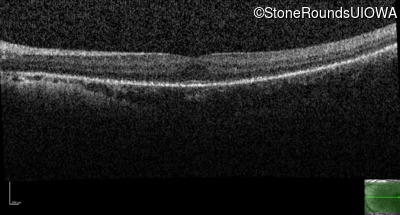

Optical Coherence Tomography - Right - 20/40 sc

Exemplar / OCT Stack

OCT Stack